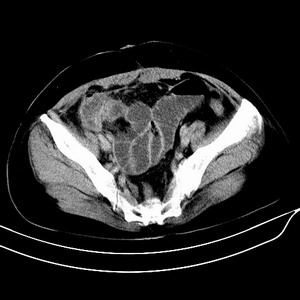

女 42岁 子宫肌瘤于外院术后两天,感腹胀。x线提示肠梗阻。

子宫肌瘤于外院术后两天,出现肠扭转梗阻,很明显。但右下腹部出现的线状高密度,是什么呢?有什么手术会有这样的物品呢?不会把电刀的导线遗留在腹腔吧!?

结果:术后纱布遗留,术后麻痹性肠梗阻肠梗阻

上面的图像是我们从手术室拿来的纱布做了个ct平扫,发现纱布里确实存在有一条致密影。后得知致密影是为防止手术时纱布遗留而设计。关腹时怀疑纱布遗留可做个床边透视或拍片可明确。